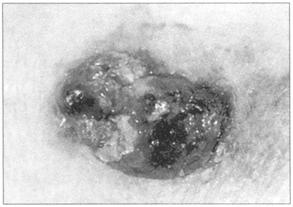

应特别注意不要漏诊有恶变倾向的痣。其特点为:形态改变;颜色不均;大于1cm;有出血;瘙痒。

请看良性色素痣(图236),不典型痣(图237),恶性黑素瘤(图238),基底细胞癌(图239)的病变。

图238 恶性黑色素瘤